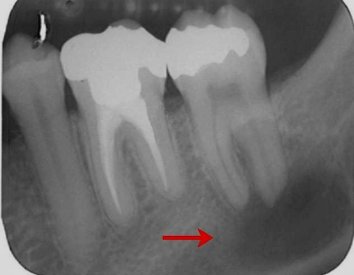

All'esame radiografico, sia l'Ascesso che il Granuloma sono rappresentati da  un'area di ridotta densità ossea, visibile come un'areola scura in prossimità dell'apice radicolare.